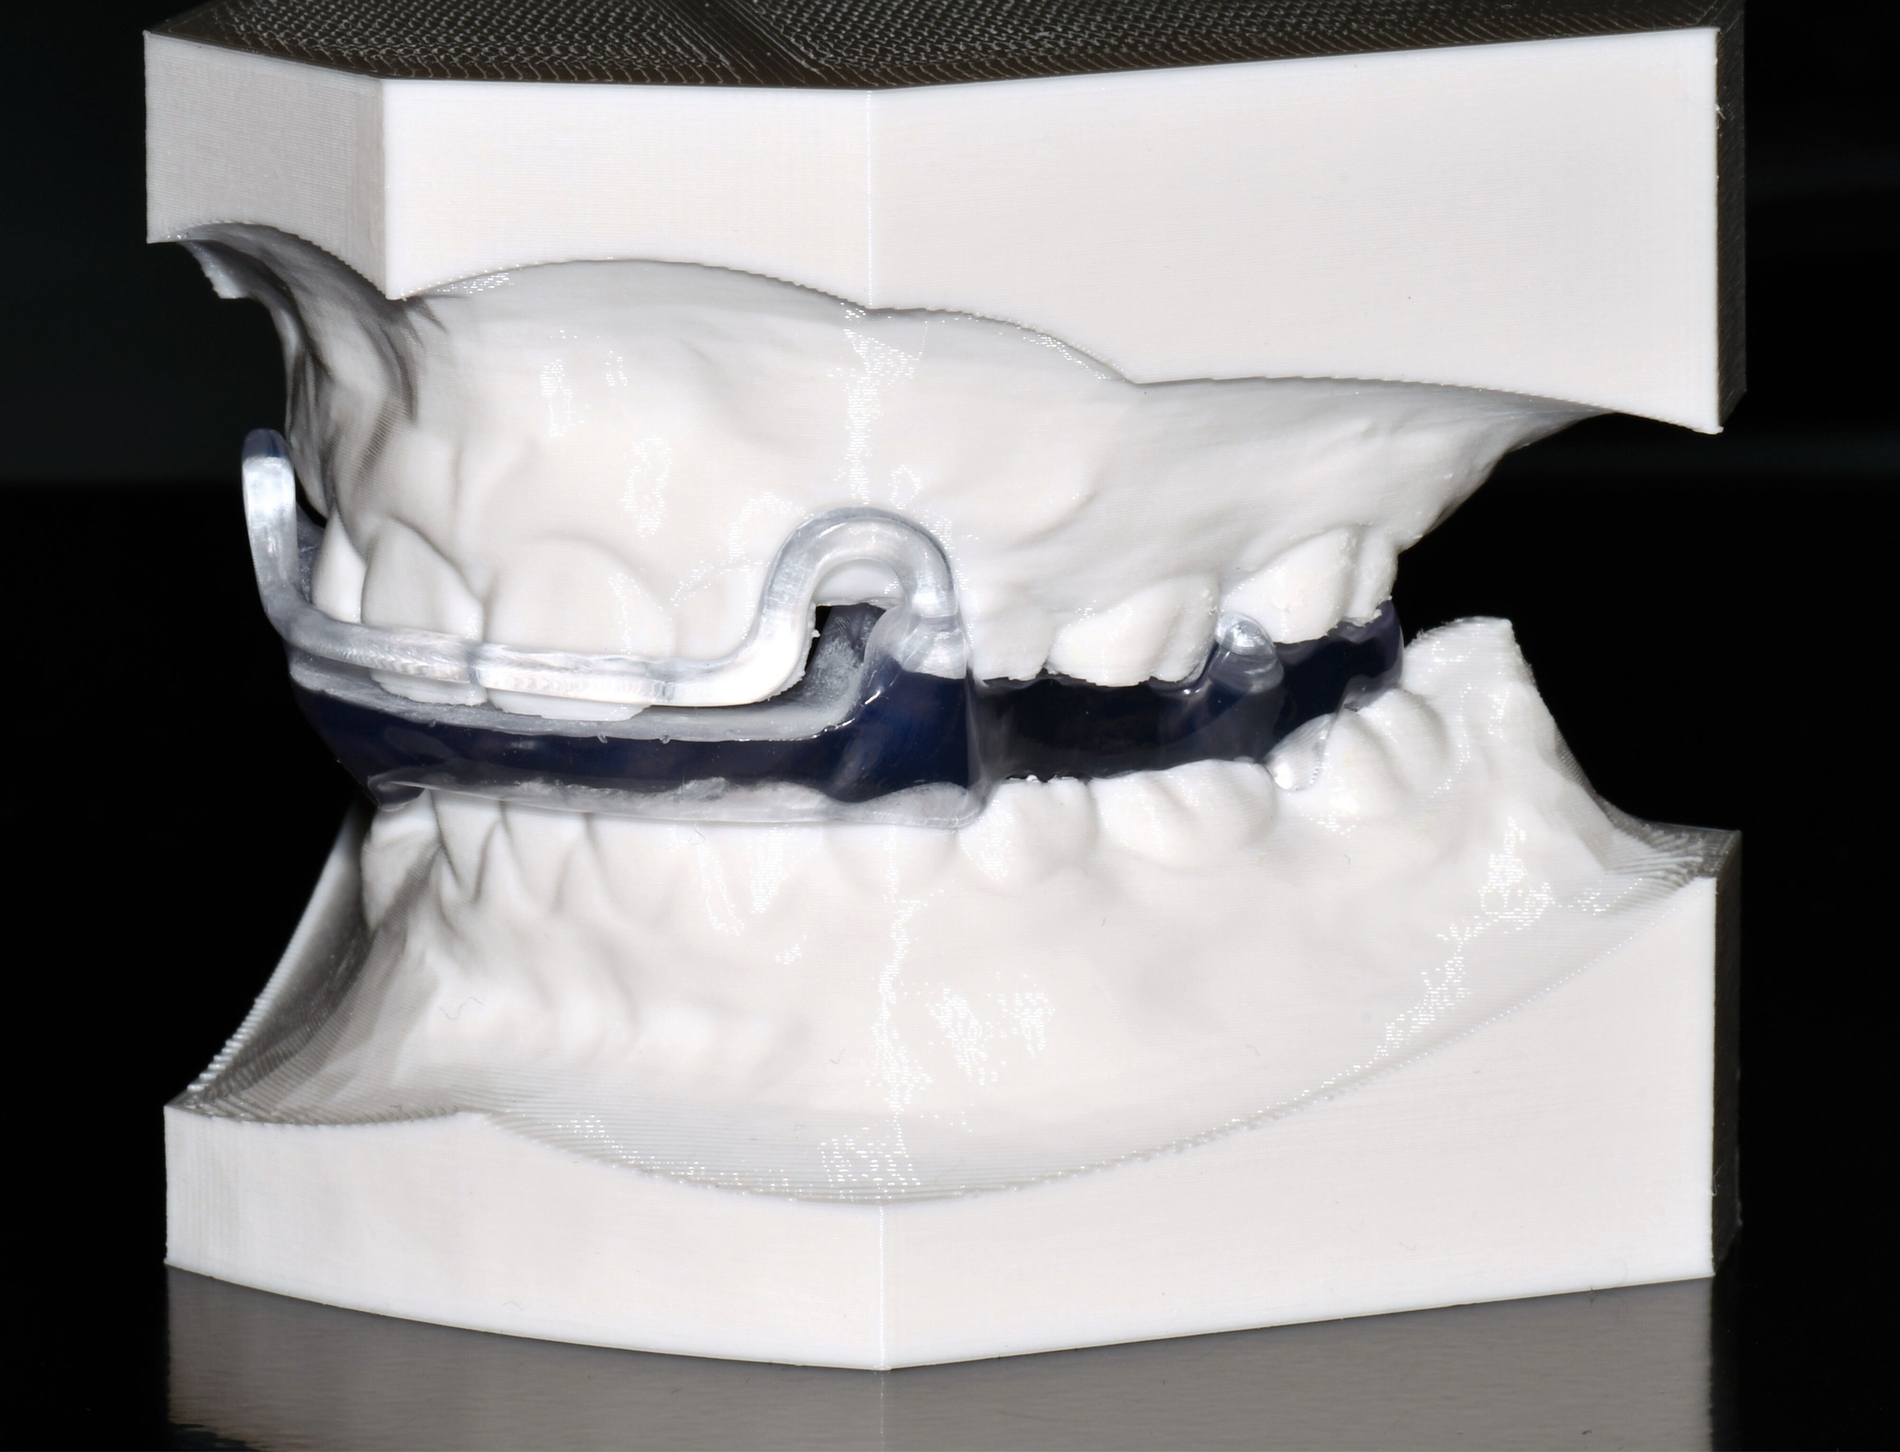

Aligner

Unter den digital gefertigten kieferorthopädischen Apparaturen sind Aligner wohl das bekannteste Beispiel [Ercoli et al., 2014, Robertson et al., 2020]. Die Herstellung von Alignern selbst basiert(e) jedoch auf einer manuellen Fertigung anhand 3-D-gedruckter Modelle und stellt(e) somit bisher eher eine partiell automatisierte Fertigung dar. Die neuesten Entwicklungen erlauben mittlerweile eine Fertigung im direkten 3-D-Druckverfahren [Tartaglia et al., 2021], so dass mühsame, zeitaufwendige Zwischenschritte der manuellen Fertigung entfallen (Abbildung 1a). Weiter profitieren die Patienten von individuelleren Fertigungsmöglichkeiten, da durch die Umsetzung im 3-D-Druck zusätzliche Elemente einfacher und stabiler in den Aligner inkorporiert werden können (Abbildung 1b).